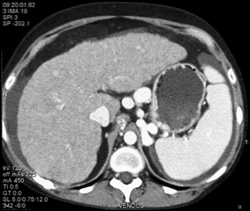

Focal Nodular Hyperplasia (FNH)